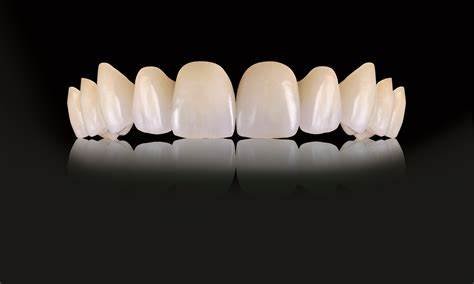

Restorative Materials for Worn Dentition

| Product | Company | Indications | Advantages |

Filtek Supreme Ultra ![]() | 3M ESPE | Direct composite restorations | Excellent wear resistance, esthetics |

IPS e.max ![]() | Ivoclar Vivadent | Ceramic crowns and veneers | High strength, natural appearance |

VITA ENAMIC ![]() | VITA Zahnfabrik | Hybrid ceramic restorations | Combines flexibility and durability |

Tetric EvoCeram Bulk Fill ![]() | Ivoclar Vivadent | Posterior restorations | Rapid placement, good wear properties |